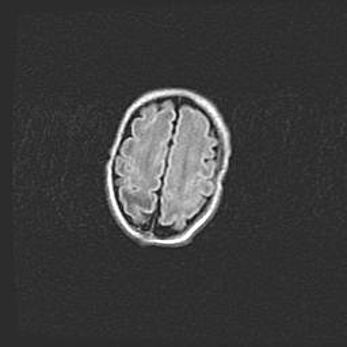

Сообщающаяся гидроцефалия. Кистозная энцефаломаляция головного мозга.

Возраст: 3 месяца 4 дня

Вес: 3100 г

Пол: женский

Окружность головы: 34 см

Срок гестации: 31 неделя

Кистозная энцефаломаляция головного мозга - одна из форм поражения головного мозга в детском возрасте. Характеризуется возникновением множественных и распространённых кист в коре, белом веществе и подкорковых образованиях головного мозга у плодов, новорождённых и детей раннего возраста. Развитие кистозной энцефаломаляции связано с внутриутробной асфиксией и гипотонией, родовой травмой, тромбозом синусов, пороками развития сосудов, инфекциями, сепсисом и другими причинами. Наиболее значимые инфекционные агенты: вирусы простого герпеса, цитомегалии, краснухи, токсоплазмы, энтеробактерии, золотистый стафилококк и другие.